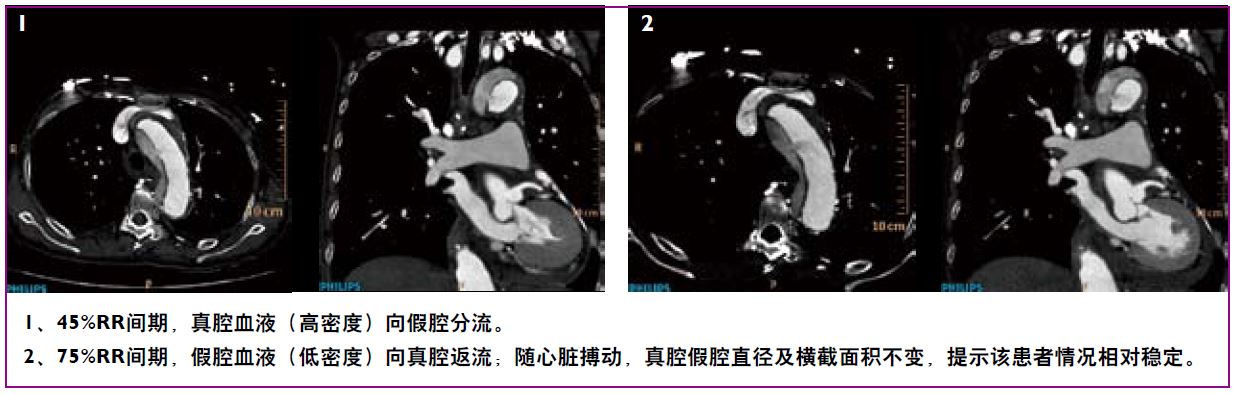

全景成像——基于宽体探测器及极速扫描实现无扫描范围限制、超低辐射剂量的高清动态全景成像,一次扫描,解剖细节及生理动态同时呈现。